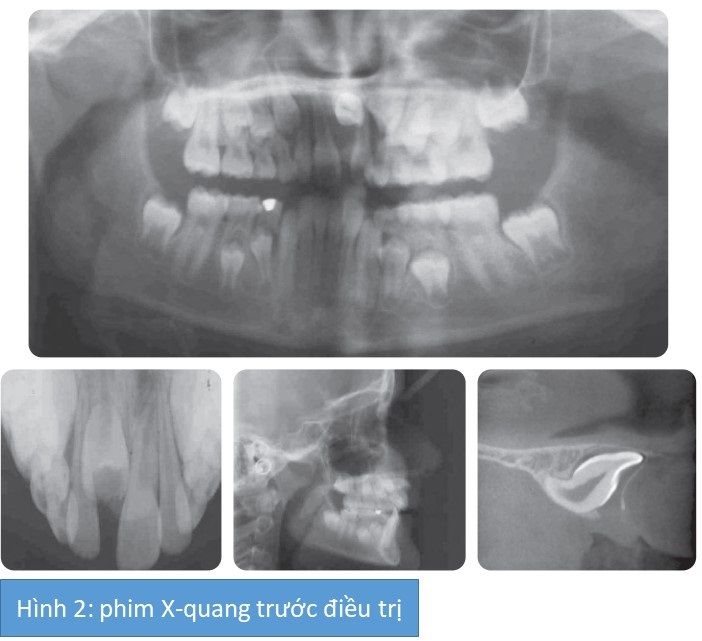

Tóm tắt các dấu hiệu X-quang (hình 2)

Tất cả các răng đều xuất hiện, gồm cả R21 và các răng hàm lớn thứ 3. R21 nằm theo hướng ngang và chân răng phát triển hoàn toàn. Không có dấu hiệu bệnh lý. Phim chụp cắt lớp vi tín với chùm tia hình nón (CBCT) xác nhận răng R21 bị lệch nhưng có tiên lượng kéo lên tốt.